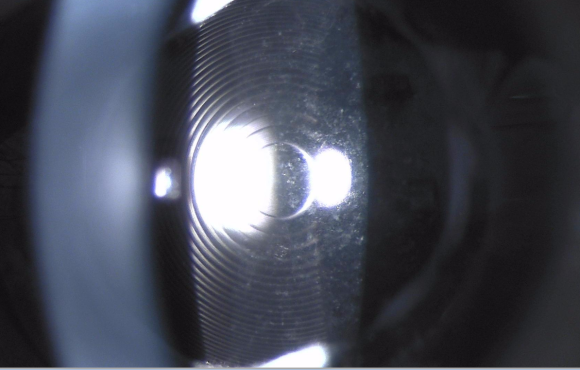

후발 백내장 모습(다초점 인공수정체) 백내장 수술은 한 번만 하면 된다고 들었습니다만, 왜 재발했습니까?우리 눈의 수정체는 얇은 수정체 낭라고 하는 캡슐에 쌓여있는 투명한 조직입니다. 백내장 수술시 캡슐은 그대로 두고 탁한 수정체만을 제거합니다.수정체 제거 후 남아있는 수정체 낭 속에 인공 수정체를 넣는 것이 백내장 수술입니다.

시간이 지나면 인공수정체가 혼탁해지는 것이 아니라 인공수정체를 포함하고 있는 수정체 낭의 뒷부분이 혼탁해지는 것이 후발백내장이며, 혼탁한 부분이 실밥을 가리면 흐릿해질 수 있습니다.

후발 백내장:인공수정체 뒤쪽에 후낭이 탁한 모습, 후발 백내장 치료는 언제 해야 합니까?후발 백내장은 백내장 수술을 받은 사람이라면 누구나 대부분 발생합니다.따라서 일생에 한 번쯤은 후발 백내장을 제거하기 위한 야구레이저 치료를 받게 됩니다.후발 백내장으로 시력 저하나 뿌옇게 보이는 등의 불쾌감을 느끼면 치료가 필요합니다.